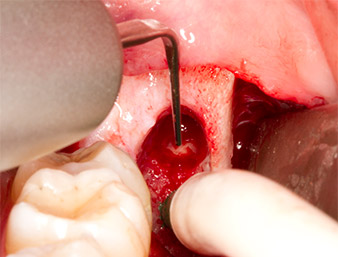

Nach Leitungs- und Lokalanästhesie wurde das Operationsfeld für einen bukkal-retromolaren Zugang weichgewebig eröffnet und dargestellt (Abb. 3).

Das Gewebe über dem Wurzelrest war nicht vollständig verknöchert und bestand zu einem großen Teil aus entzündlich verändertem Granulationsgewebe (Abb. 4).